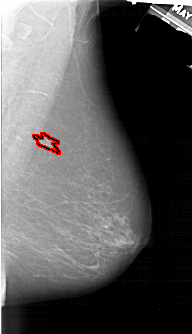

FILE: A_1501_1.RIGHT_MLO.OVERLAY

TOTAL_ABNORMALITIES 1

ABNORMALITY 1

LESION_TYPE MASS SHAPE IRREGULAR MARGINS ILL_DEFINED

ASSESSMENT 4

SUBTLETY 2

PATHOLOGY MALIGNANT

TOTAL_OUTLINES 1

BOUNDARY